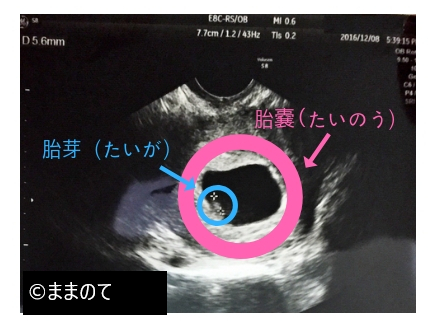

妊娠6週では、赤ちゃんの頭と胴体の区別がつくようになり、胎嚢の中には胎芽が確認できます。胎嚢の大きさは1.5~2cm程度に成長しています。

経腟超音波検査で胎芽の心拍動を見られるようになるのもこの時期です。心拍が確認されれば、最終月経の開始日や胎芽の頭からお尻までの長さを計測した「胎児頭臀長(とうでんちょう)」から正確な出産予定日を決定します。

上の画像は、筆者が第二子妊娠を妊娠したときの6週2日の胎嚢です。うっすらと卵黄嚢らしきものが確認できます。写真からはサイズはわかりません。設備が古かったのか、医師の信条によるものなのかは定かではありませんが、とにかく手元にあるのはなかなかにさっぱりとしたエコー写真のみなのです。